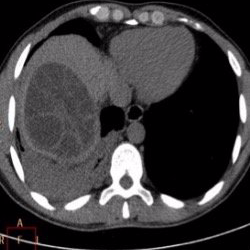

Metástasis: son implantes tumorales procedentes de cánceres originados en otro órgano. Es el tumor hepático maligno más frecuente. Aunque existen muchos tipos de cáncer que pueden causar metástasis hepáticas, los más frecuentes son los digestivos (colon, páncreas, estómago). En función de su localización y características, las metástasis hepáticas asociadas a cáncer de colon son operables, pudiendo alargar la supervivencia del paciente.